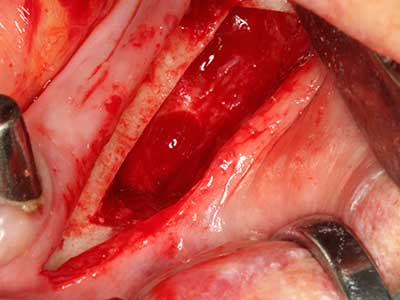

Indication: Preparations close to nerve tissue

As noted above, indications for piezo surgery can also be found in the field of conservative dental surgery. Special working tips simplify the exposure of root tips and make it easier to protect nerves and sinus mucous membranes, particularly in the lower premolar and upper posterior tooth regions. Angled diamond tips are used to precisely prepare the resection cavity for the retrograde root filler material for unsealed apical obturation. The ultrasonic technology means the tips can be very slender, which improves the view and the size of the access cavity. As a result, the application of ultrasonic surgery for this indication is one of the standard procedures for apical resection (Del Fabbro, Tsesis et al. 2010, Scarano, Artese et al. 2012).

Indication: Apical resection

When surgical procedures are performed on bone in the immediate vicinity of sensitive structures such as blood vessels or nerves, rotary instruments pose a significant risk of iatrogenic injury. Piezoelectric devices can be helpful for preparation of bone covers and removal of hard tissue close to nerves, particularly for exposure of nerves after iatrogenic injury but also during nerve lateralization for resective and reconstructive procedures or implant placement (Fig. 17-20). Light contact between the piezotip and the nerve does not generally result in damage but proceeding incautiously with saw-like motions or attachments where a residual bone substrate remains may cause temporary or even permanent nerve damage. However, the risk of damage is considered to be substantially lower than when using saws or milling instruments (Pereira, Gealh et al. 2014).